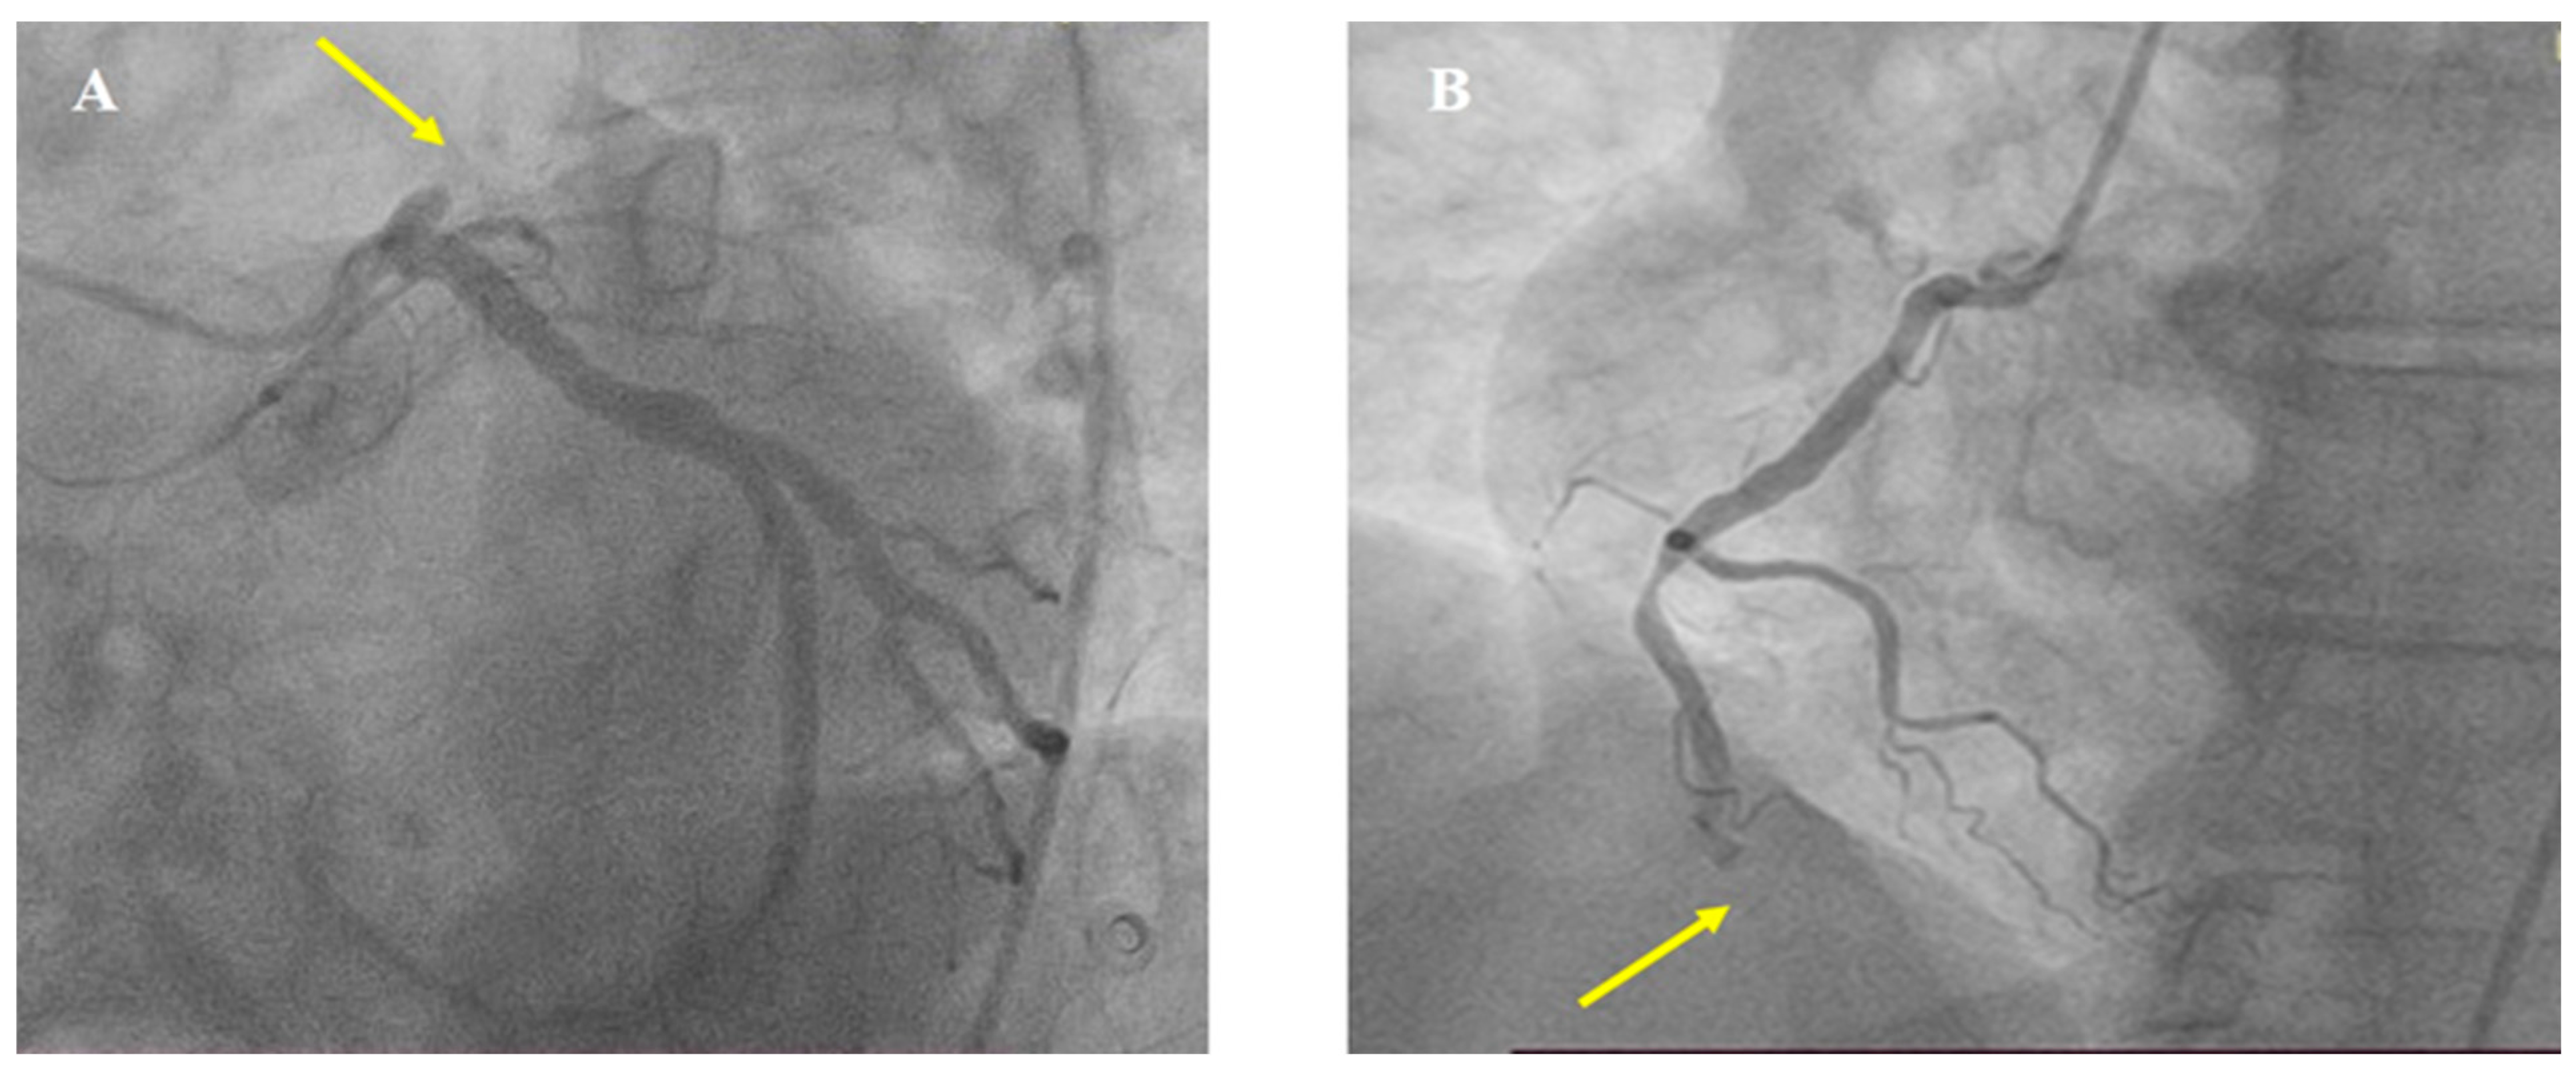

2. Case Report